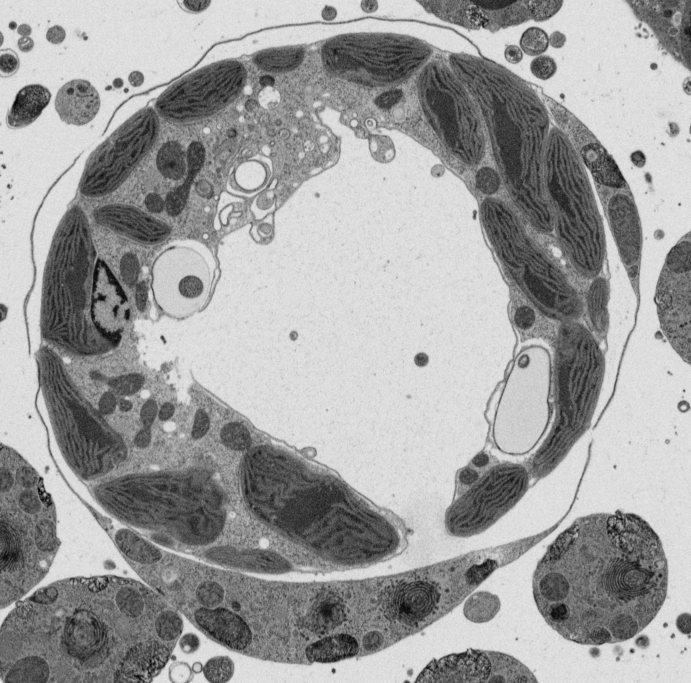

Actual z-index: 319Sampling: sampled from 632 source slicesScale: 20 x 20 x 20 nmContrast: source uint8. 8-bit source planes are written directly without intensity renormalization.Frame cache: warming 0/96Keyboard: ←/→ step, Home/End jump.